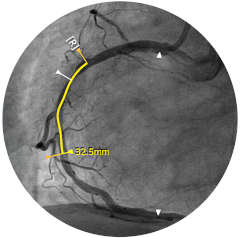

Presentamos la nueva plataforma de aplicaciones intervencionistas Philips IntraSight, en la que la imagen, la fisiología, el corregistro* y el software se unen para facilitar una atención óptima del paciente. IntraSight ofrece un conjunto completo de modalidades clínicamente probadas, como la iFR/FFR, la IVUS y el corregistro* para simplificar las intervenciones complejas, acelerar los procedimientos rutinarios y proporcionar una mejor atención al paciente.

Construida sobre una plataforma inteligente basada en aplicaciones que puede escalar para satisfacer las necesidades cambiantes de su laboratorio cuando se disponga de nuevas aplicaciones o modalidades, sin necesidad de adquirir nuevo hardware. Solo Philips IntraSight ofrece las mejores herramientas de imagenología y fisiología de su clase con iFR, corregistro iFR*, FFR, IVUS, corregistro IVUS* y Angio+*. Con su arquitectura modular, IntraSight se mantiene a la vanguardia de los últimos avances y actualizaciones de seguridad importantes.

Figura 2